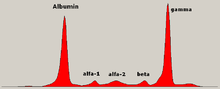

The presence of unexplained anemia, kidney dysfunction, a high erythrocyte sedimentation rate (ESR), lytic bone lesions, elevated beta-2 microglobulin, and/or a high serum protein (especially raised globulins or immunoglobulin) may prompt further testing. The globulin level may be normal in established disease. A doctor will request protein electrophoresis of the blood and urine, which might show the presence of a paraprotein (monoclonal protein, or M protein) band, with or without reduction of the other (normal) immunoglobulins (known as immune paresis). One type of paraprotein is the Bence Jones protein which is a urinary paraprotein composed of free light chains (see below). Quantitative measurements of the paraprotein are necessary to establish a diagnosis and to monitor the disease. The paraprotein is an abnormal immunoglobulin produced by the tumor clone.

In theory, multiple myeloma can produce all classes of immunoglobulin, but IgG paraproteins are most common, followed by IgA and IgM. IgD and IgE myeloma are very rare. In addition, light and or heavy chains (the building blocks of antibodies) may be secreted in isolation: κ- or λ-light chains or any of the five types of heavy chains (α-, γ-, δ-, ε- or μ-heavy chains). Patients without evidence of a monoclonal protein may have "nonsecretory" myeloma (not producing immunoglobulins); this represents approximately 3% of all multiple myeloma patients.[17]

Other useful laboratory tests include quantitative measurement of IgA, IgG, IgM (immunoglobulins) to look for immune paresis, and beta-2 microglobulin which provides prognostic information. On peripheral blood smear the rouleaux formation of red blood cells is commonly seen, though this is not specific.

The recent introduction of a commercial immunoassay for measurement of free light chains potentially offers an improvement in monitoring disease progression and response to treatment, particularly where the paraprotein is difficult to measure accurately by electrophoresis (for example in light chain myeloma, or where the paraprotein level is very low). Initial research also suggests that measurement of free light chains may also be used, in conjunction with other markers, for assessment of the risk of progression from monoclonal gammopathy of undetermined significance (MGUS) to multiple myeloma.

This assay, the serum free light chain assay, has recently been recommended by the International Myeloma Working Group for the screening, diagnosis, prognosis, and monitoring of plasma cell dyscrasias.